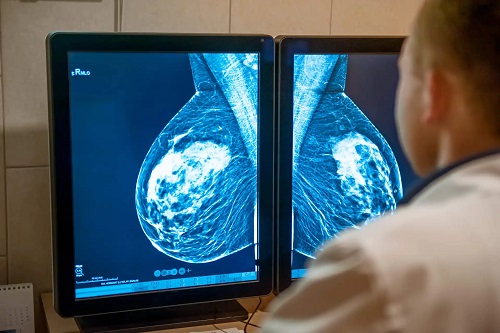

Înainte de începerea tratamentului, este nevoie de un CT sau un RMN pentru a crea o hartă tridimensională a tumorii. Oncologii sunt responsabili de calcularea modului de livrare a tratamentului în dozele optime și în locul potrivit.